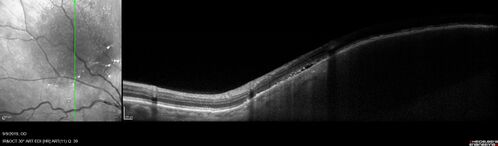

Amelanotic Choroidal Nevus - Multimodal Imaging

61 year old man with amelanotic choroidal nevus. Vision Normal - Stable over 4 years.